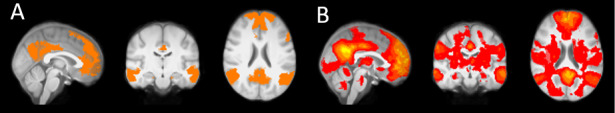

Morningness is associated with several positive health outcomes and personality traits such as conscientiousness. In the current report, meta-analysis demonstrated a significant association between morningness and conscientiousness, data that are consistent with previous meta-analyses. Further, survey report and resting-state functional Magnetic Resonance Imaging (rs-fMRI, N = 43) indicated that the relationship between morningness and conscientiousness was moderated by functional connectivity with the Default Mode Network (DMN). DMN connectivity has been implicated in a number of cognitive functions and higher connectivity in this network is associated with higher conscientiousness.